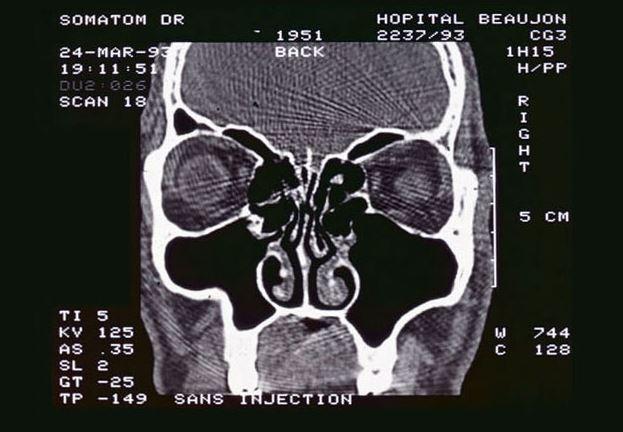

| Koreus | Une aiguille de 12 centimètres dans le visage |

Un médecin retire une aiguille de 12,5 cm di visage d'un homme

5 inch in pin pulled from my face

@Anthooo C'est quand meme en dessous du cerveau hein

Je sais pas trop ce qu'il y a par la. Les fosses nasales ? ![]() Mais impressionnant !

a mon avis c est un genre de broche que lui retire le medecin que lui meme a mis la

C'est bien le cas, c'est une aiguille mécicale. Apparement il avait l'os de l'orbite de l'oeil cassé . Donc ca a permis de soigné